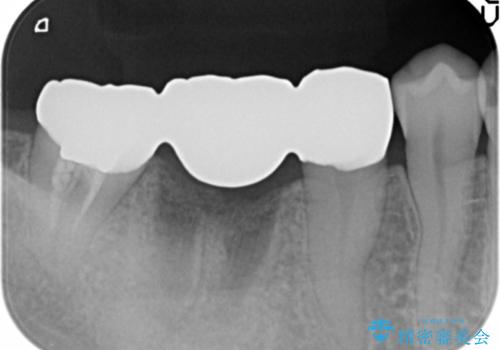

抜歯後はセラミックブリッジを用いた咬合機能回復を計画します。

- 24万円(仮歯・フルジルコニアクラウン×3)費用は治療当時の料金となります

インプラント治療に比べブリッジ治療は比較的短期に手術の必要なく終えることができます。